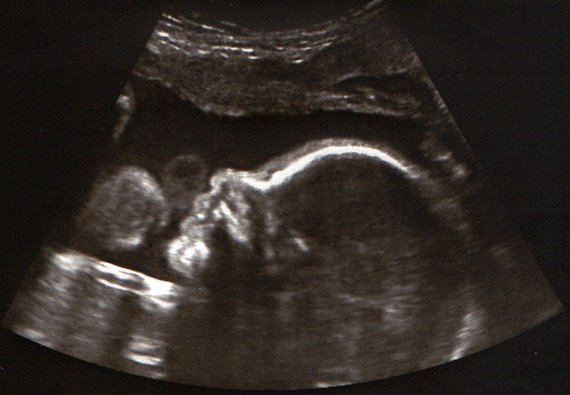

Bebe 27 semaine-Fiks Fare, Sa e besojnë qytetarët programin e LSIsë '1000 $ për bebe', 27 Janar 21, Pjesa 1 27/01/21 2102Cette échographie biométrique permet de s'assurer du bon développement des organes de votre enfant et mesure le diamètre de sa tête, en vue de l'accouchement Votre médecin en profitera pour vous confirmer la position de votre bébé S'il n'est pas encore retourné, il pourra tenter de le faire manuellement, à travers votre ventre

Echographie De Bebe A 27 Sa 4 Jours Le 16 01 09 Ma Deuxieme Grossesse Apres Une Greffe De Rein

Echographie Affective 27 Sa 2 Petit Bout D Amour

Echo 27 Sa Profil Bebe Grossesse Fraisechocolats Photos Club Doctissimo